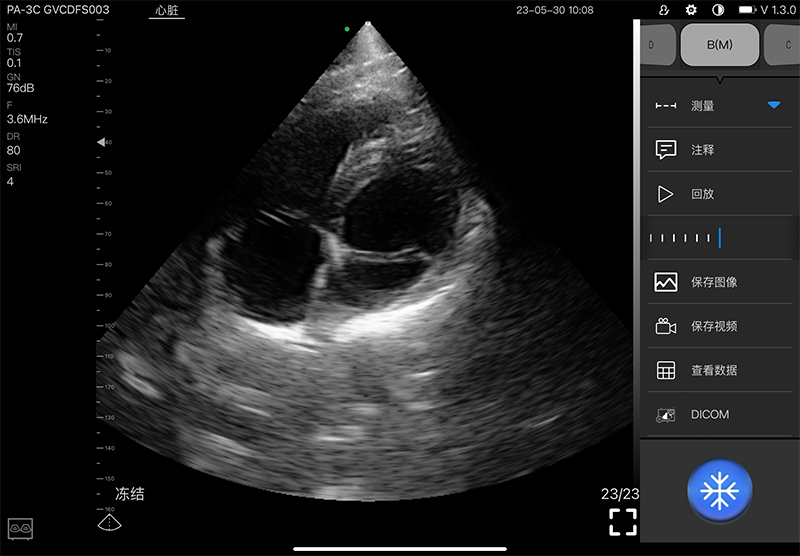

5PA

5PA Plus

- Scanning mode: Electronic phased array

- Display mode: B, B/M, and Color, PW, CW, PDI

- Frequency: central 2.8MHz, cardiac reverse harmonic

3.6mhz, and the transcranial fundamental 2.2MHz

- Display Angle: 80°